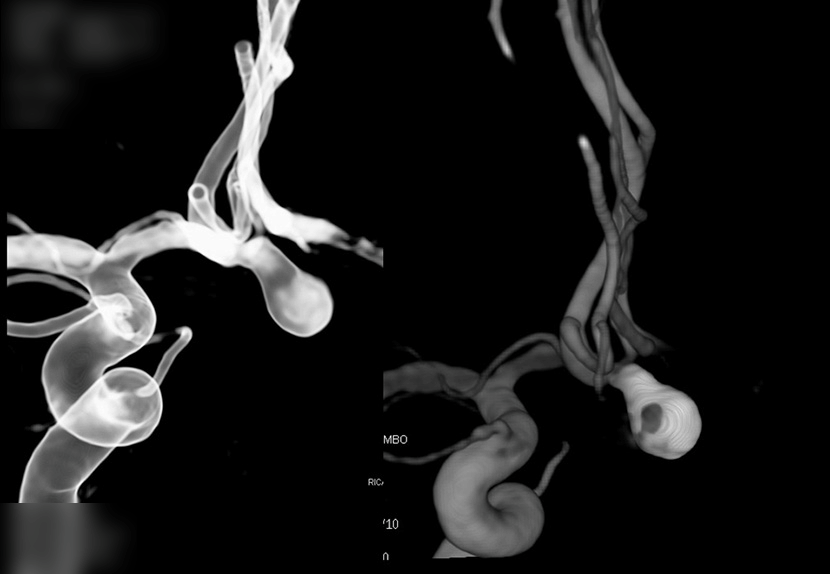

수술전 CT혈관조영술에서 전교통동맥의 비파열성 뇌동맥류 발견

혈관내 코일색전술 후 동맥류 내부에 코일이 들어가 있는 모습